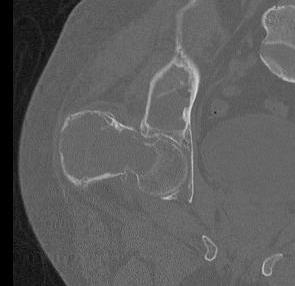

X-ray

Intramedullary lucent diaphyseal lesion with 'ground glass appearance'

- thinned, slightly bulged cortex

- ± endosteal scalloping

- may have angular deformity / bowing

Coxa vara and Shepherd's Crook deformity of proximal femur

- Shepherd's Crook - anterior bowing of femur

CT